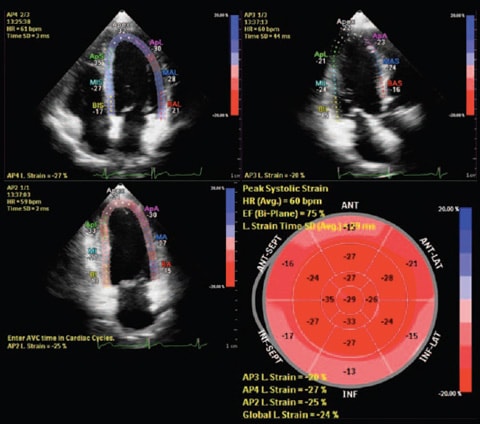

Anatomische Intelligenz wendet adaptive Systemintelligenz mit anatomischen 3D-Modellen auf die Ultraschalldaten eines Patienten an, um schnell und einfach reproduzierbare Ergebnisse zu liefern. Mit fortschrittlichen Funktionen für die Organmodellierung, Erstellung von Schnittbildern und Quantifizierung ermöglicht die Anatomische Intelligenz eine einfachere Durchführung und bessere Reproduzierbarkeit von Ultraschalluntersuchungen und liefert gleichzeitig aussagekräftige klinische Ergebnisse, um den wirtschaftlichen und klinischen Herausforderungen der heutigen Gesundheitsumgebung gerecht zu werden.

Höhere Diagnosesicherheit durch bessere Reproduzierbarkeit mit weniger Arbeitsschritten in geringerer Zeit im Vergleich zu herkömmlichen Verfahren

Anatomische Intelligenz kommt bei Philips Bildgebungslösungen wie EPIQ Affiniti und EchoNavigator zum Einsatz und stattet Klinikteams mit ausgereiften aber dennoch benutzerfreundlichen Verarbeitungstools aus. Dabei ermöglicht sie die zuverlässige Identifizierung von anatomischen Strukturen und Anomalien die Beurteilung des Krankheitsstatus die Ermittlung der passenden Behandlung und die Durchführung geführter Eingriffe in kürzester Zeit.